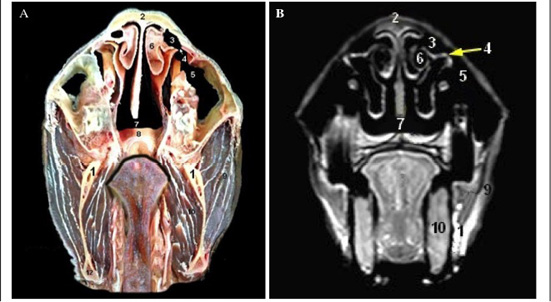

Cross sectional anatomy (Panel A) and MR image (Panel B) of horse head at the level of first and second premolar teeth. 1) Upper first and second premolar teeth; 2) Lower first and second premolar teeth; 3) Cartilaginous part of Nasal septum; 4) maxilla bone; 5) Nasal bone; 6) Dorsal nasal meatus; 7) Middle nasal meatus; 8) Ventral nasal meatus; 9) Dorsal nasal concha; 10) Ventral concha1 bulla; 11) Body of tongue; 12) Buccinators muscle.

Cross sectional anatomy (Panel A) and MR image (Panel B) of horse head at the level of the third premolar tooth. 1) Upper third premolar tooth; 2) Lower third premolar tooth; 3) Dorsal turbinate crest of Nasal bone; 4) Ventral turbinate crest of maxilla bone; 5) Palatine process of Maxilla; 6) Dorsal nasal concha; 7) Ventral nasal concha (bulla); 8) Common nasal meatus; 9) Superior labii levator muscle; 10) Geniohyoid muscle.